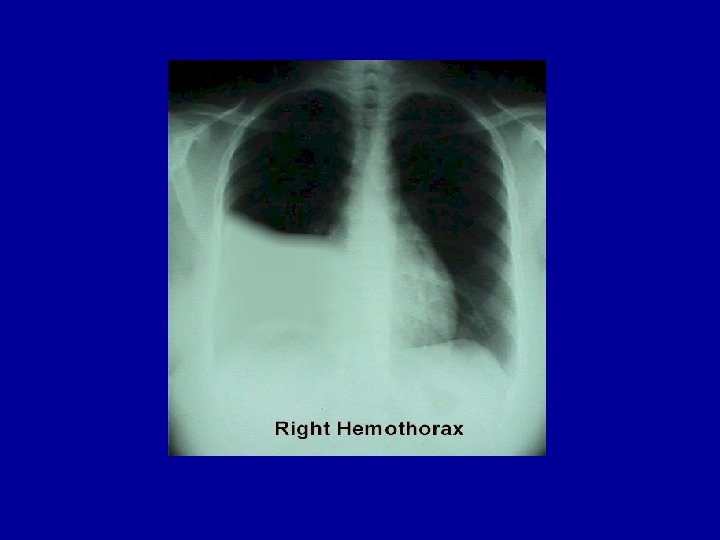

Other Laboratory Findings in ARF CXR Abnormalities Complete Blood Count (look at WBC and Hgb, which may suggest chronic hypoxia) Electrolyte Abnormalities (look at bicarbonate)

Pneumothorax